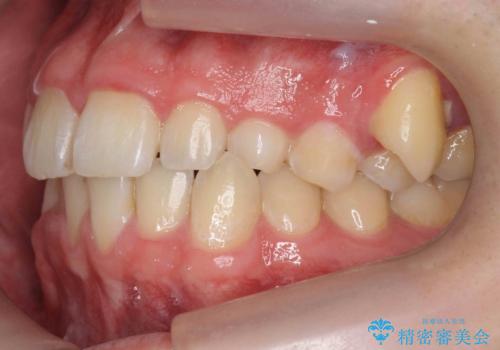

前歯のすき間、犬歯の異所萌出 乳歯を抜かずに矯正

- 前歯のすきまと八重歯を主訴に来院。

左上の乳犬歯が残っており、その下から生えてくるはずの犬歯(永久歯)が左上小臼歯部に萌出していました。

左上の乳犬歯は根もしっかりしていたため、

を提案し、➀を選択されました。

将来的にインプラントは希望されないとのことだったため、乳歯の部分は隙間を開けてインプラントを入れる用のすき間を確保するということは特に行いませんでした。

乳歯をそのまま並べたため、上顎の左右の犬歯の幅は非対称になっています。